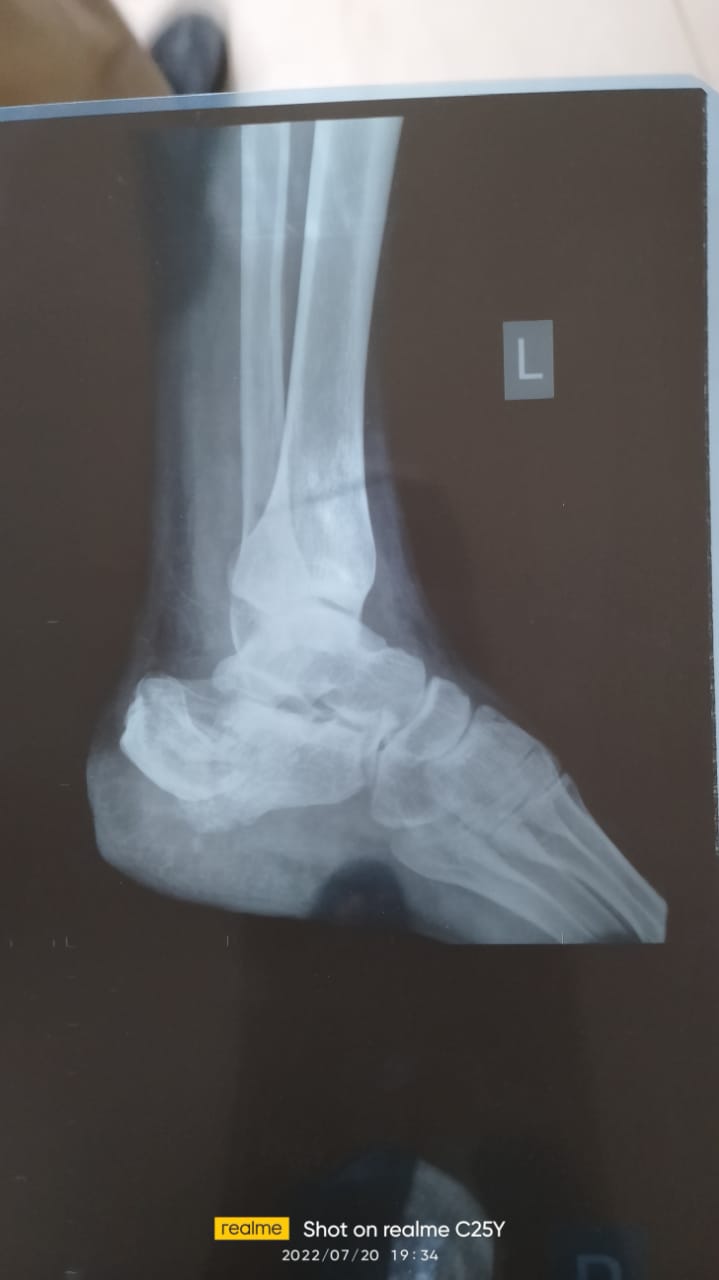

وأوضح شقيق المصاب، في تصريحات خاصة لـ القاهرة 24، أنه قد ذهب رفقة شقيقه بعدما حملته عربة الإسعاف من مدينة العاشر من رمضان وجرى تحرير المحضر اللازم بالواقعة، وتم نقل المصاب إلى مستشفى بلبيس المركزي، لتلقي الإسعافات اللازمة، وهناك تبين خطورة حالته ليتم تحويله إلى أحد المستشفيات لإجراء تدخل جراحي، قبل أن يتبين حاجته لتركيب 16 مسمارا طبيا وشريحتين جراء إصابته التي تحتاج نحو ثلاثة أشهر للعلاج.